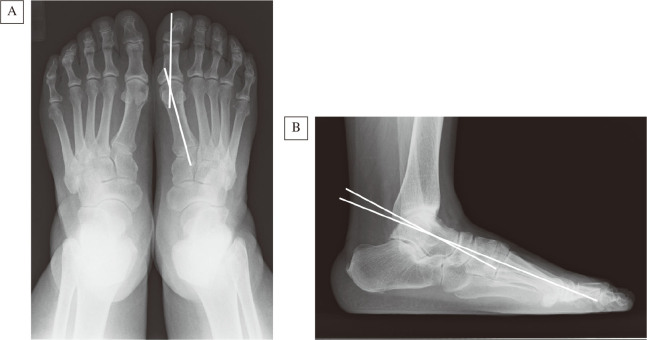

We compared the relationship between foot alignments and quality of life in patients who underwent initial total knee arthroplasty (TKA). Among the patients with knee osteoarthritis (KOA) who underwent TKA from May 2015 to May 2017 at our hospital, we focused on those in whom weight-bearing foot radiographs had been evaluated preoperatively. The hallux valgus angle and Meary angle were measured by preoperative radiography, and those with hallux valgus angles of 20 degrees or more were classified into the hallux valgus (HV) group, and those with Meary angles of 4 degrees or more into the high arch (HA) group. Also knee and ankle range of motion, knee pain Visual Analog Scale, and the 36-item short-form health survey (SF-36) were measured preoperatively and at discharge, and the amount of these changes was compared in the presence/absence of HV and HA. Regarding HV, there were no significant differences in any of these items between the HV and non-HV groups. However, the SF-physical function was significantly lower in the HA group than in the normal group. In addition, ankle dorsiflexion was lower in the HA group than that in the normal group, although this difference was not statistically significant. There was little improvement of the ankle dorsiflexion, and it was associated with deterioration of the physical function items of SF-36. In total knee arthroplasty patients with HA, physical therapy of the ankles and feet, as well as of the knees, was considered to enhance the improvement of physical function.